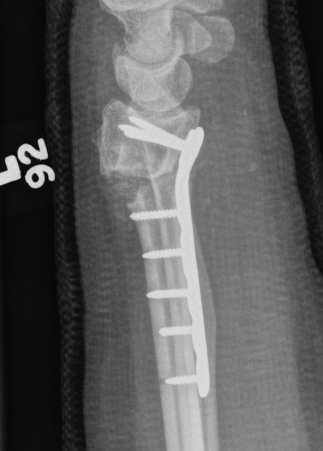

Dorsal opening wedge osteotomy

Advantage

Lengthens the distal radius

May be easier to correct in coronal and sagittal plane

Disadvantage

Dorsal approach / dorsal plate - extensor tendon issues

Technique

3 / 4 dorsal approach

- expose distal radius

- can use half pins to control distal fragment

- protect structures with homan retractors

- osteotomy with microsagittal saw

- correct radial articular surface in sagittal & coronal planes

- trapezoidal bi-cortical iliac crest autograft / synthetic graft

- dorsal locking plate